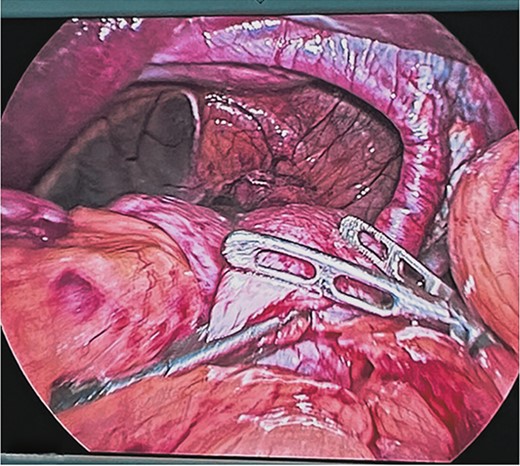

At the end of the dissection of both diaphragmatic crura, their plasty was performed by placing six single 2-0 polypropylene suture stitches with an atraumatic needle with extracorporeal knots at both ends of the hiatus, reducing its size to 5 cm. Subsequently, a composite mesh with a resorbable coating was fixed with automatic laparoscopic staples, reducing the hiatus by up to 3 cm (Fig. 5). Finally, a Toupet fundoplication was performed as an anti-reflux mechanism (Fig. 6).

Modeling of Toupet fundoplication with intracorporeal technique with polypropylene suture 2-0.